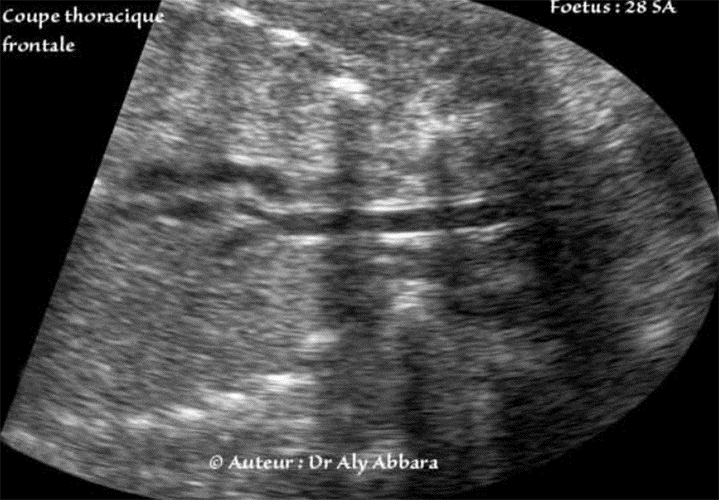

Coupe frontale du haut du thorax et du cou

(Fœtus âgé de 28 SA).

• Coupes échographiques thoraciques frontales (coronales) centrées sur la partie supérieure et postérieure du thorax ; elles permettent la mise en évidence la trachée occupant le centre du cou et du médiastin, de son origine au niveau cervical, jusqu'à sa division (bifurcation) en deux bronches (droite et gauche) près du bord gauche de la crosse de l'aorte.

• La trachée est identifiable sur ces coupes grâce à son diamètre non négligeable, son contenu anéchogène, et sa paroi à dédoublement échogène.